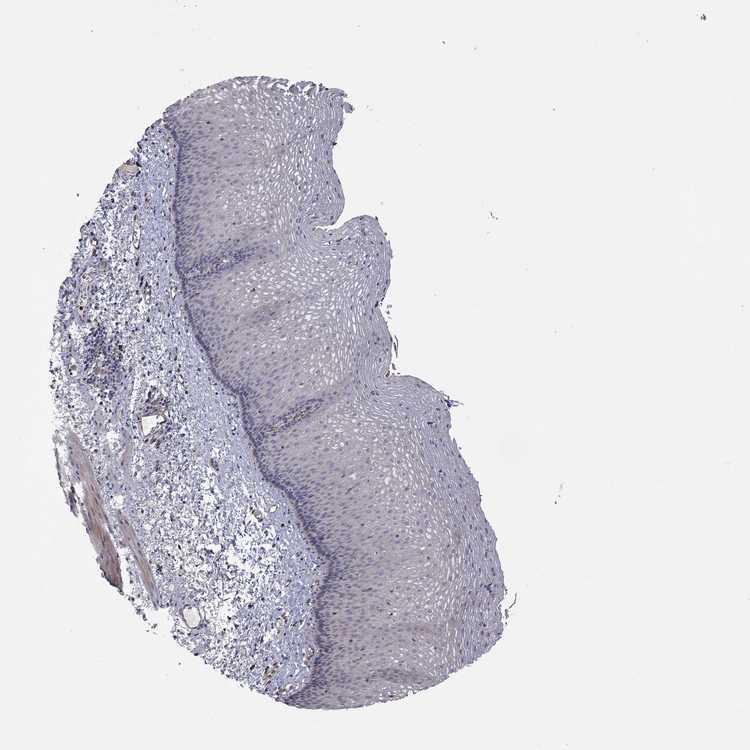

ESOPHAGUS - Antibody stainingi

Antibody staining in the annotated cell types in the current human tissue is reported as not detected, low, medium, or high, based on conventional immunohistochemistry profiling in selected tissues. This score is based on the combination of the staining intensity and fraction of stained cells.

Each image is clickable and will lead to virtual microscopy that enables deeper exploration of all samples and also displays staining intensity scores, fraction scores and subcellular localization as well as patient and tissue information for each sample.

Antibody HPA017345Antibody HPA064805

Squamous epithelial cells Not detectedNot detected